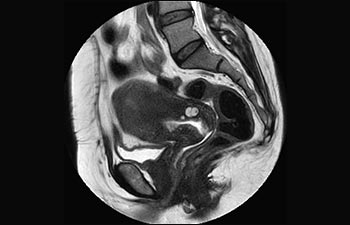

Enhanced diagnostic confidence in neuro oncology

Find the right clinical applications for your needs